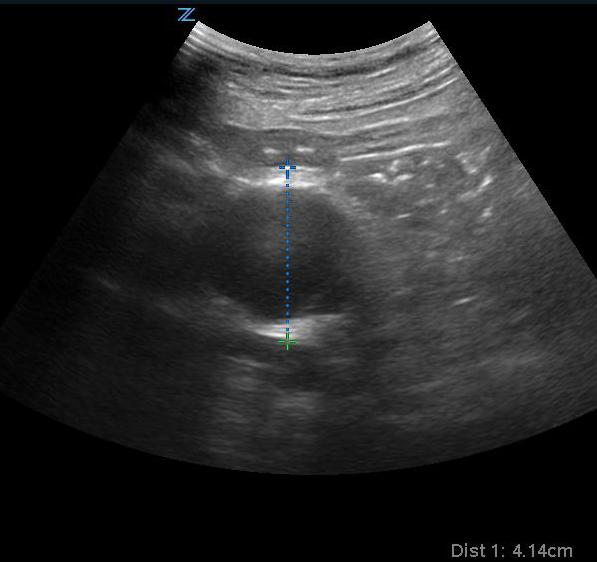

- Aorta and iliac arteries are measured from outer wall to outer wall. Normal abdominal aorta diameter is less than 3 cm. AAA is defined as greater than 3 cm.

- At least 3 transverse views, labeled, “proximal”, “mid”, “distal” with calipers should be recorded. One view should show the maximal aortic diameter.

- Figure 3. Transverse view of the proximal aorta

- AAA is described as being a focal dilatation of the abdominal aorta of 150% of normal.12-13 Although there is no established definition of aneurysm size, conventionally, an AAA is diagnosed when the diameter exceeds 3.0 cm.14

- Figure 7. Transverse view of a 4.1 cm AAA

- Video 4. Transverse view of large AAA

- Video 5. Longitudinal view of large AAA